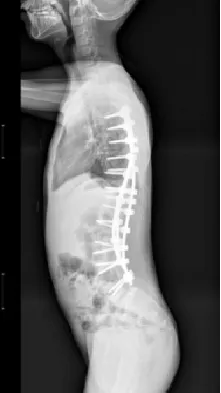

▲ 男,14岁,早发性脊柱侧弯、先天性脊柱畸形

▷退变性脊柱侧凸